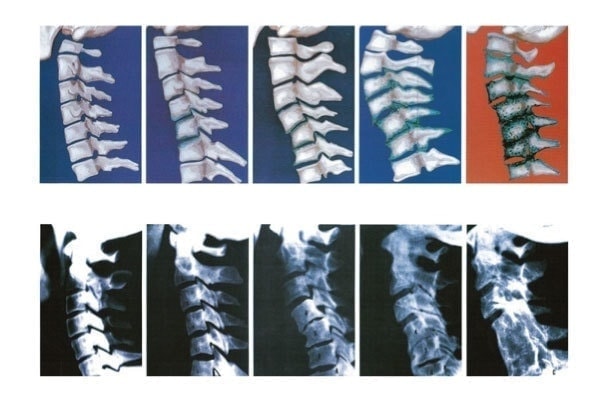

こちらの写真は頚椎の変性の具合を示していますが、椎間板周りの骨の状態が徐々に悪化しています。

なぜ、このように変性していくのか?

それは猫背やストレートネックなどのゆがみが生じていると頚椎ひとつひとつが正常に機能せず、動きの悪くなった関節は代謝が低下していくためです。

変性と呼ばれる現象は、誰しもが起こりうる変化ですが、骨格のゆがみは変性を助長してしまいます。